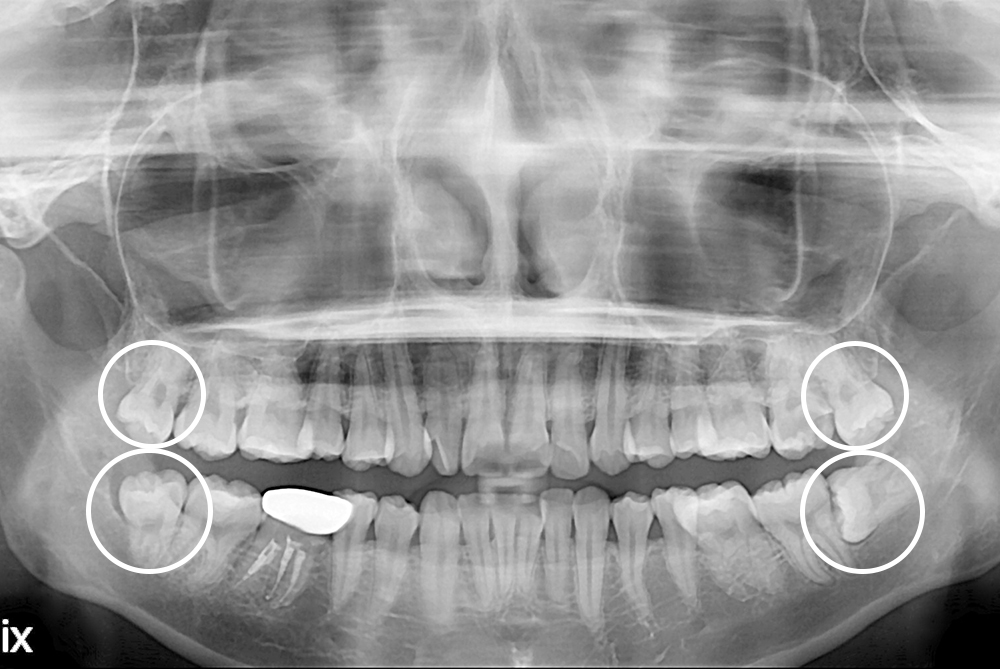

[사랑니] 매복 사랑니 발치

치료전 : 2019-02-08